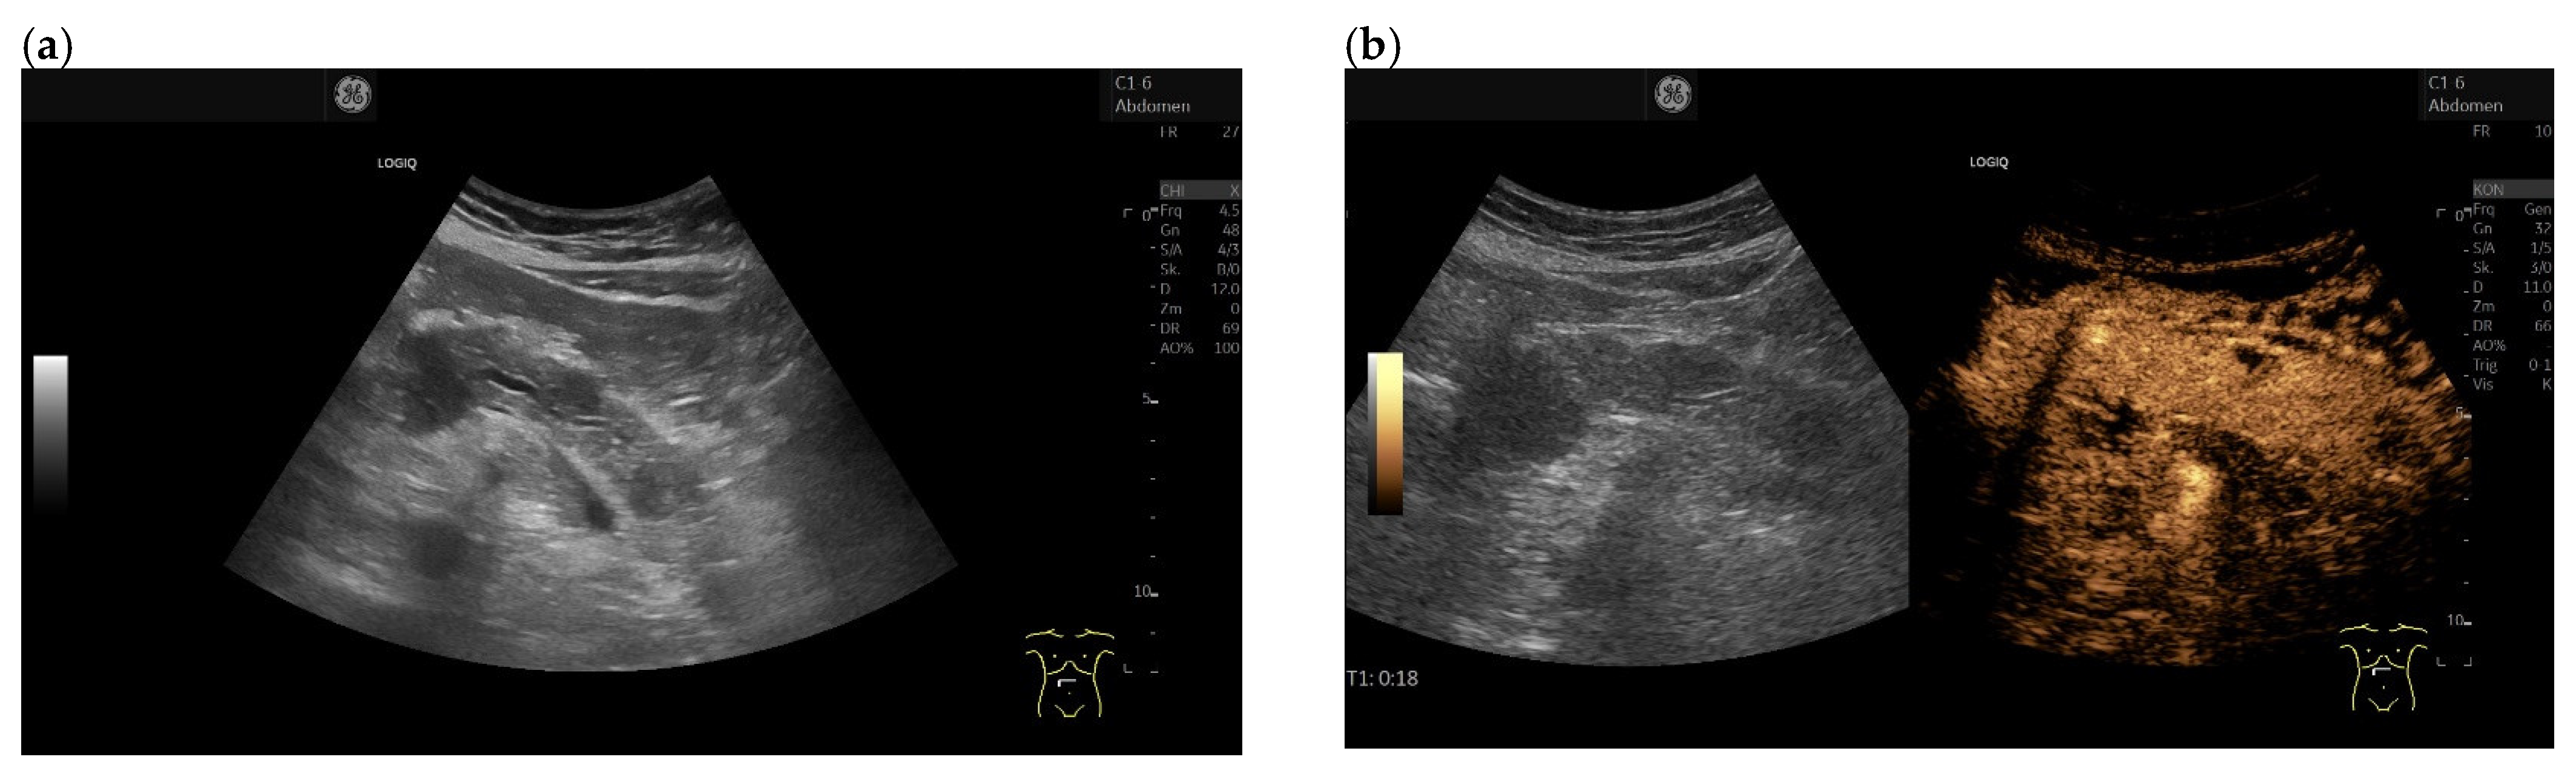

3.4. CEUS and CH-EUS

- De Robertis, R.; D’Onofrio, M.; Crosara, S.; Dal Corso, F.; Barbi, E.; Canestrini, S.; Mucelli, R.P. Contrast-enhanced ultrasound of pancreatic tumours. Australas. J. Ultrasound Med. 2014, 17, 96–109. [Google Scholar] [CrossRef]

- D’Onofrio, M.; Barbi, E.; Dietrich, C.F.; Kitano, M.; Numata, K.; Sofuni, A.; Principe, F.; Gallotti, A.; Zamboni, G.A.; Mucelli, R.P. Pancreatic multicenter ultrasound study (PAMUS). Eur. J. Radiol. 2012, 81, 630–638. [Google Scholar] [CrossRef]